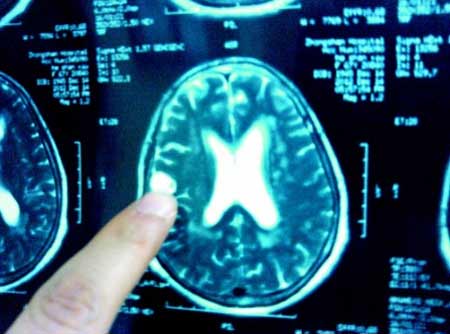

Ổ trùng được chụp từ trong não bệnh nhân

Bà Hà là một giáo viên nghỉ hưu ở Hồ Bắc, ngày 10/12 , bà đột ngột bị hoa mắt chóng mặt và nôn mửa nhiều lần. Ngày 14/12, đi khám thì bác sĩ phát hiện tắc mạch máu não và được chuyển lên bệnh viện Trung Sơn tỉnh Hồ Bắc (Trung Quốc). Sau khi trải qua hàng loạt kiểm tra hóa nghiệm, bác sỹ phát hiện trong não có 2 khối di động trong não và chứa đầy sán.

Theo bác sĩ Bành, Trưởng khoa nội thần kinh bệnh viện Trung Sơn, thông thường, sau khi người bệnh ăn phải thực phẩm có các nang sán, các nang này sẽ bám theo hệ thống tĩnh mạch và đường ruột và cuối cùng “định cư” ở não bộ và phát triển thành sán. Hoạt động của những con sán này sẽ phá hủy mô não, từ đó gây ra đau đầu, nôn mửa hoặc chứng động kinh.